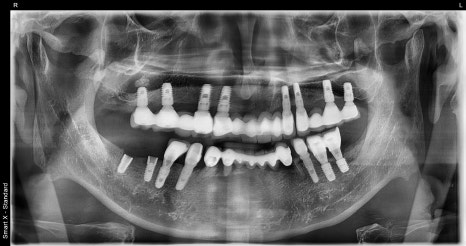

왼쪽 사진: 치료 전 전체 엑스레이입니다. 아래쪽엔 파절된 임플란트가, 위쪽엔 기존 임플란트 보철 상태가 보입니다.

치료가 완료된 후 파노라마 엑스레이입니다. 임플란트가 안정적으로 유착되었고 교합도 잘 맞는 상태입니다.